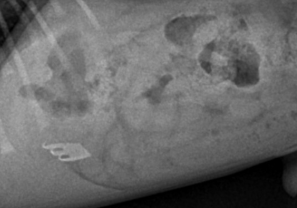

반려동물이 나이 들어갈수록 가장 자주 마주하게 되는 질병 중 하나, 종양.특히 악성종양(암)으로 인한 사망률이 30–40%에 달할 만큼 임상적 비중이 큰 분야입니다.